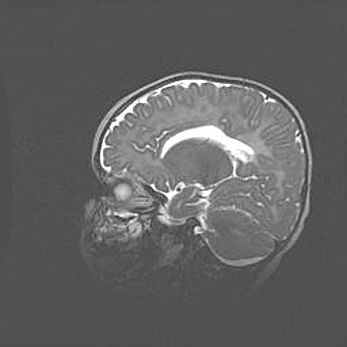

Наружная гидроцефалия с возможной атрофией височных областей.

Возраст: 28 дней

Вес: 3670 г

Пол: мужской

Окружность головы: 38 см

Срок гестации: 40 недель

Гидроцефалия головного мозга у новорожденных – это заболевание, которое характеризуется скоплением избыточного количества спинномозговой жидкости в желудочковой системе головного мозга в результате затруднения её перемещения от места выработки к месту поглощения в кровеносную систему или вследствие нарушения абсорбции. При открытой наружной форме гидроцефалии у новорожденных расширяются и переполняются субарахноидные пространства.

При нормотензивных  формах,  которые,  как  правило,  являются  следствием  перенесенных ишемических  повреждений  паренхимы  мозга,  возможно  сочетание микроцефалии  с нормотензивной гидроцефалией. В основе данных изменений лежит атрофия больших полушарий с преимущественной  локализацией  в  лобно-височных  областях.